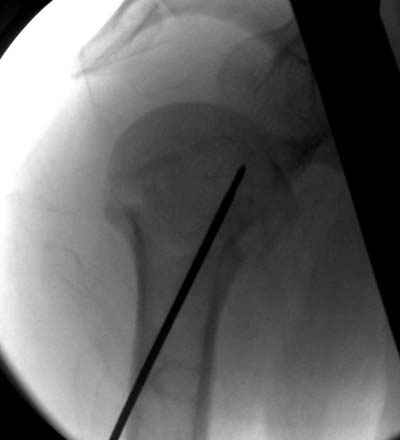

Клинические снимки - 3 недели после операции

Посылаю послеоперационные Рг граммы.

Поздравляю, получилось просто замечательно. Если можно, расскажи чуть подробнее, как делали - как вправляли, как вводили спицы, поворачивали ли их?

Спасибо за поздравления:-))

Я и сам доволен результатом. В предпоследнем письме я кратко описал ход операции - закрыто репонировать не удалось( 2 недели с момента травмы и 1 неделя после неудачной репозиции) после удаления пучков спиц, пришлось сделать - 2см разрез на уровне перелома и с помощью периостального элеватора (золотое правило механики) *одеть* головку на дистальный отломок.

Спицы проводил через старые отверстия, вращая пучок импактором- направителем при его введении в головку.